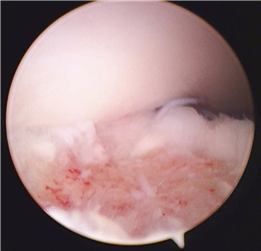

Clinical & Radiographic Imaging Archive

Clinical Image